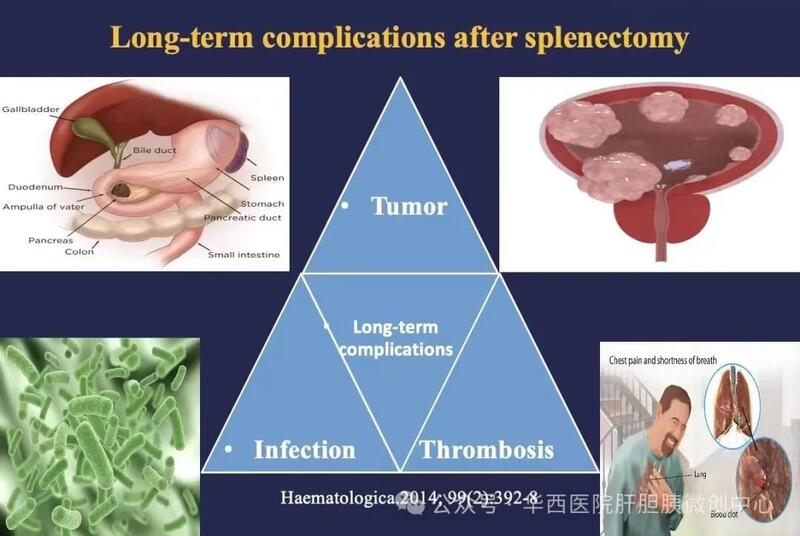

脾脏是人体重要的免疫器官,它参与血液的过滤、免疫细胞的生成和储存、以及血液成分的调节,具有 抗感染、抗肿瘤、抗血栓 等作用。在某些疾病或外伤情况下,脾脏可能需要切除。然而,传统的脾脏全切除术可能会增加患者罹患肿瘤、感染、血栓形成等风险。因此,保留脾脏功能的手术显得尤为重要。

切脾的远期并发症

1, 最大限度保留了正常脾脏的体积和功能,或几乎不丢失正常脾脏组织,能够较好地维持脾脏的生理功能,使脾脏的免疫、滤过 及储血功能不至于丧失;血栓风险、远期出现凶险性感染或爆发性感染的几率也因此降低。